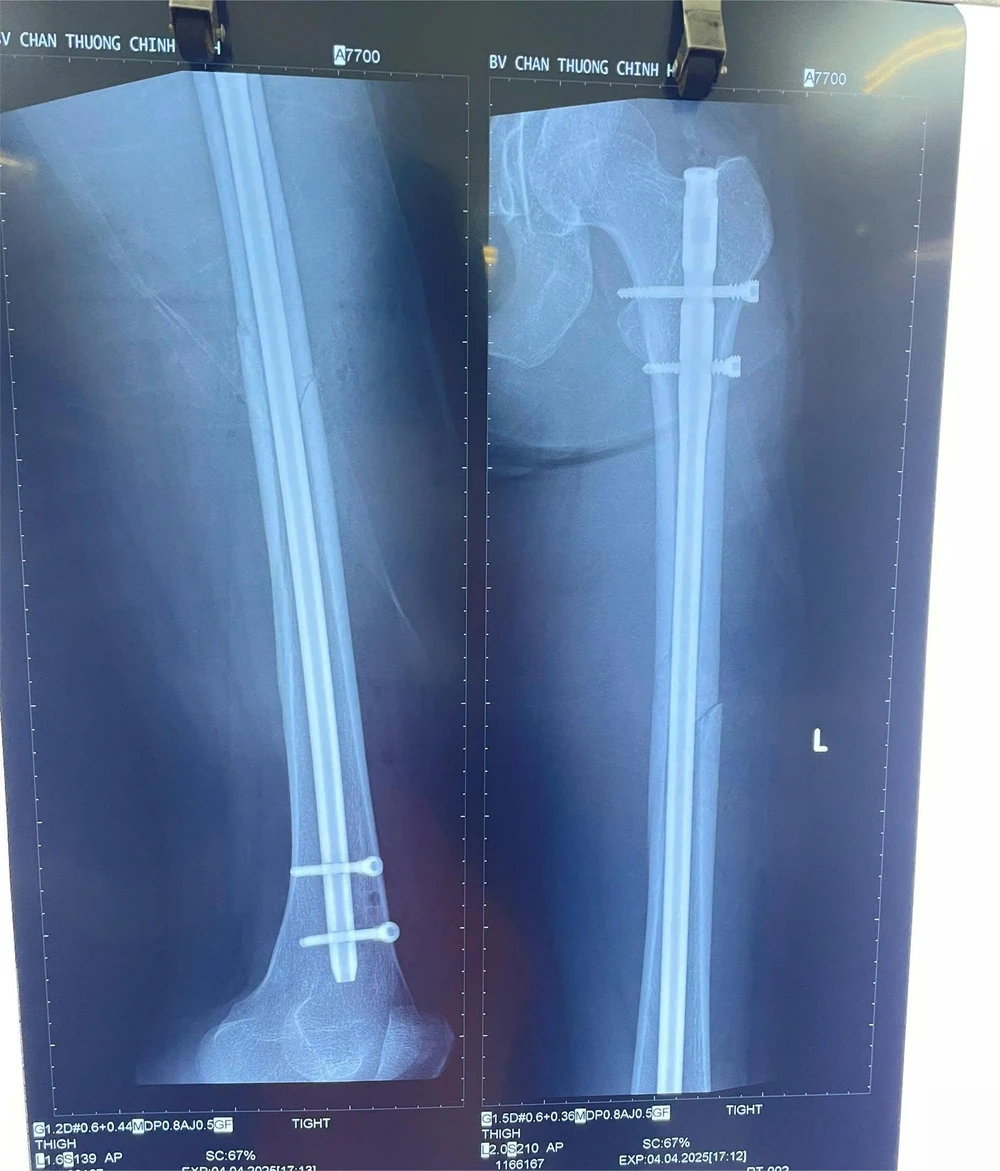

Kết quả chụp X-quang cho thấy cô bị gãy 1/3 giữa thân xương đùi bên trái.

Bệnh nhân bị chấn thương gãy chân, bác sĩ phải thực hiện đường mổ nhỏ, tránh ảnh hưởng thẩm mỹ cho người bệnh. Ảnh: BVCC

Theo bác sĩ Thắng, ca mổ của bệnh nhân này rất khó, bởi bệnh nhân cao đến 1m78, đường gãy xương tét dọc xuống theo xương đùi trái, nhiều đường chồng lên nhau.

Vì vậy bác sĩ phải thực hiện đường mổ nhỏ, tránh ảnh hưởng thẩm mỹ cho người bệnh, nhưng phải đảm bảo đủ nắn chỉnh cố định để chống chân đi được sau một ngày phẫu thuật.